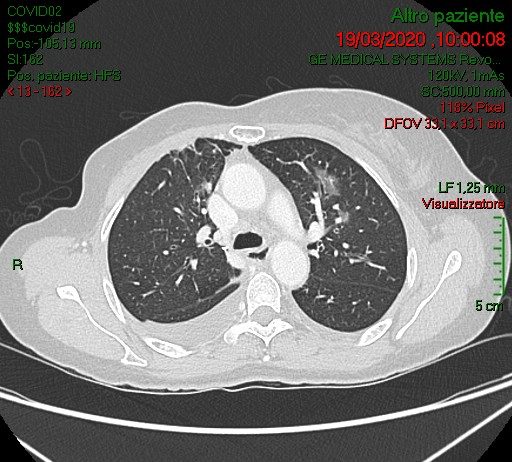

Femmina, 58 anni, asintomatica e apiretica.Esegue come paziente ambulatoriale esterna TC total body per controllo oncologico in neoplasia mammaria, sottoposta nel 2006 a mastectomia con linfoadenectomia, trattata con CT neoadiuvante e RT.